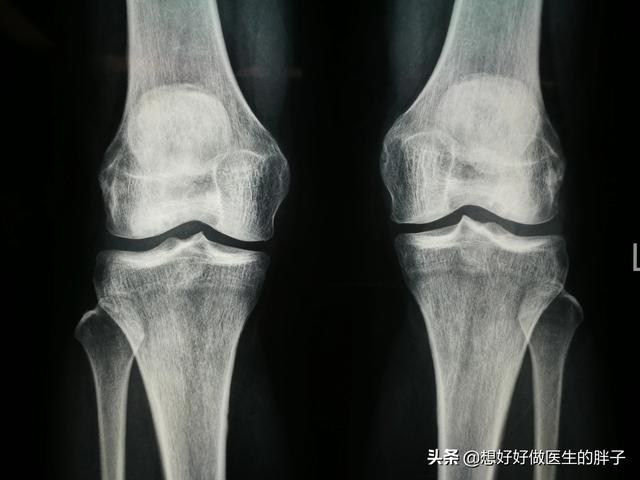

Wenn der Patient unter Gelenkschmerzen aufgrund von Arthrose leidet, empfiehlt es sich, entsprechende Untersuchungen im Krankenhaus durchzuführen, wobei die meisten VoruntersuchungenRöntgenfilm des KniesAnhand der Röntgenbilder können wir feststellen, ob der Patient eine schwerefetthaltige KnochenbildungIst dieStenose des Gelenkspaltsund gibt eine erste Einschätzung des Zustands des Knies.

Der Arzt wird in der Regel anhand von Röntgenbildern und einer MRT-Untersuchung des Knies feststellen, in welchem Stadium sich der Patient befindet.

Röntgenaufnahmen bestätigen das Vorhandensein von Gelenkspaltverengungen, Überlastungen der Gelenke und Sklerose der Gelenkflächen des gesamten Kniegelenks.